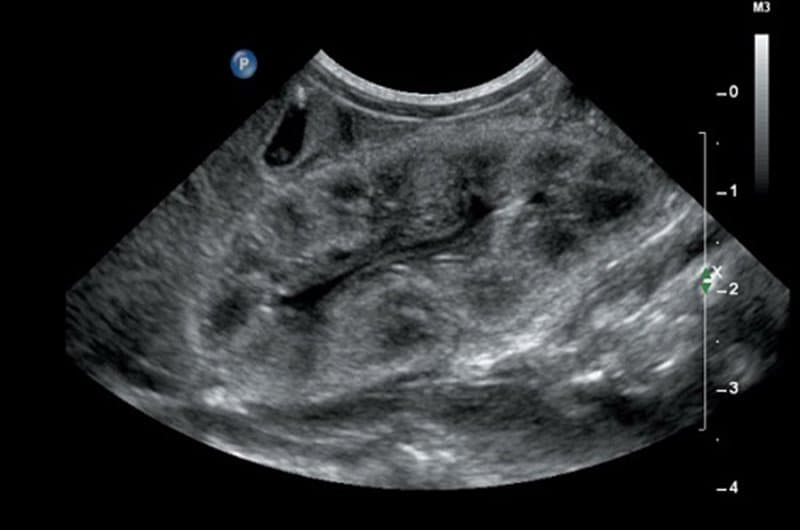

Ultrasound is a common diagnostic imaging test used to look inside the human body. Now it has started being used to examine the stomach for various diseases, but mainly it is often used in pregnant women to see the child.

Ultrasound uses sound waves to create images of the inside of the body. It is a painless and safe test that can be used to look at different parts of the body.

In this, sound waves captured by the transducer pass through an object and return after colliding. Due to which the scanned image remains on the screen. The transducer looks like a microphone that sends sound waves to the organ during testing. Captures echoes for the display image.